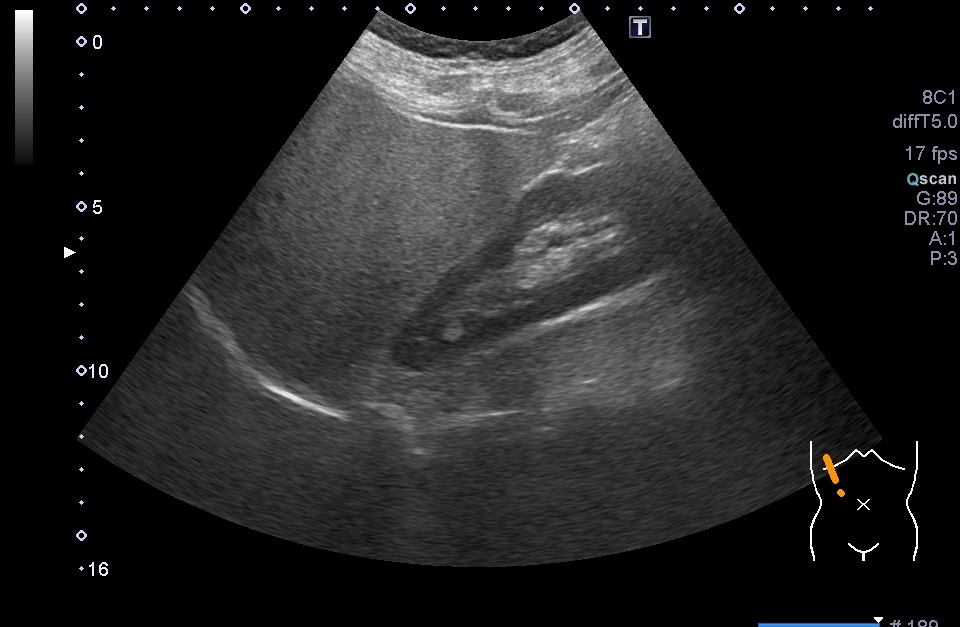

最近は、ご自分で妊娠反応を確かめてみえるかたも多いですが、妊娠の確定診断には超音波検査が必要です。妊娠反応の感度がとてもよくなったため、妊娠反応がでても超音波で赤ちゃんをいれている袋が見えない時期というのが数日から1週間程度あります。妊娠週数の計算法は、生理がはじまって14日目に排卵がおこっていることを前提としているため、超音波で赤ちゃんが見えない場合には、「実際に排卵したのは14日目よりも遅く、病院にくるのがはやかったのでみえない」「妊娠は成立したが、何らかの理由で正常に進行していない」「異所性(子宮外妊娠)」の3つの場合があります。

妊娠週数は最後の生理が始まった日から数えて280日目を分娩予定日とし、週数で数えます。28日周期で生理が合っている方だと、4週0日が次の生理の予定の日となります。 おおむね5-6週で、赤ちゃんのはいっている袋(胎嚢)がみえてきます。赤ちゃんの心拍がみえるようになるのが7週前後です。8週から11週にかけての赤ちゃんの大きさを計測して、生理から計算した分娩予定日とのずれが大きければ予定日を修正します。そしてその後は母子手帳をお渡しして、いわゆる妊婦健診を開始します。